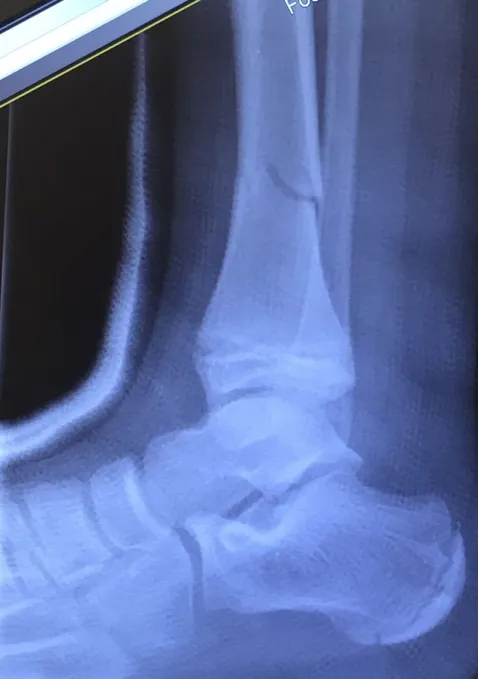

Pictures below show a 60 year old woman who fell getting out of bed and broke the shaft of her tibia as has a distal fibular fracture. This was treated with an Intramedullary rod as well as a surgical plate and fixation with screws of the fibular fracture.

Displaced Tib-fib fracture that was treated with IM rod of the Tibia (below)